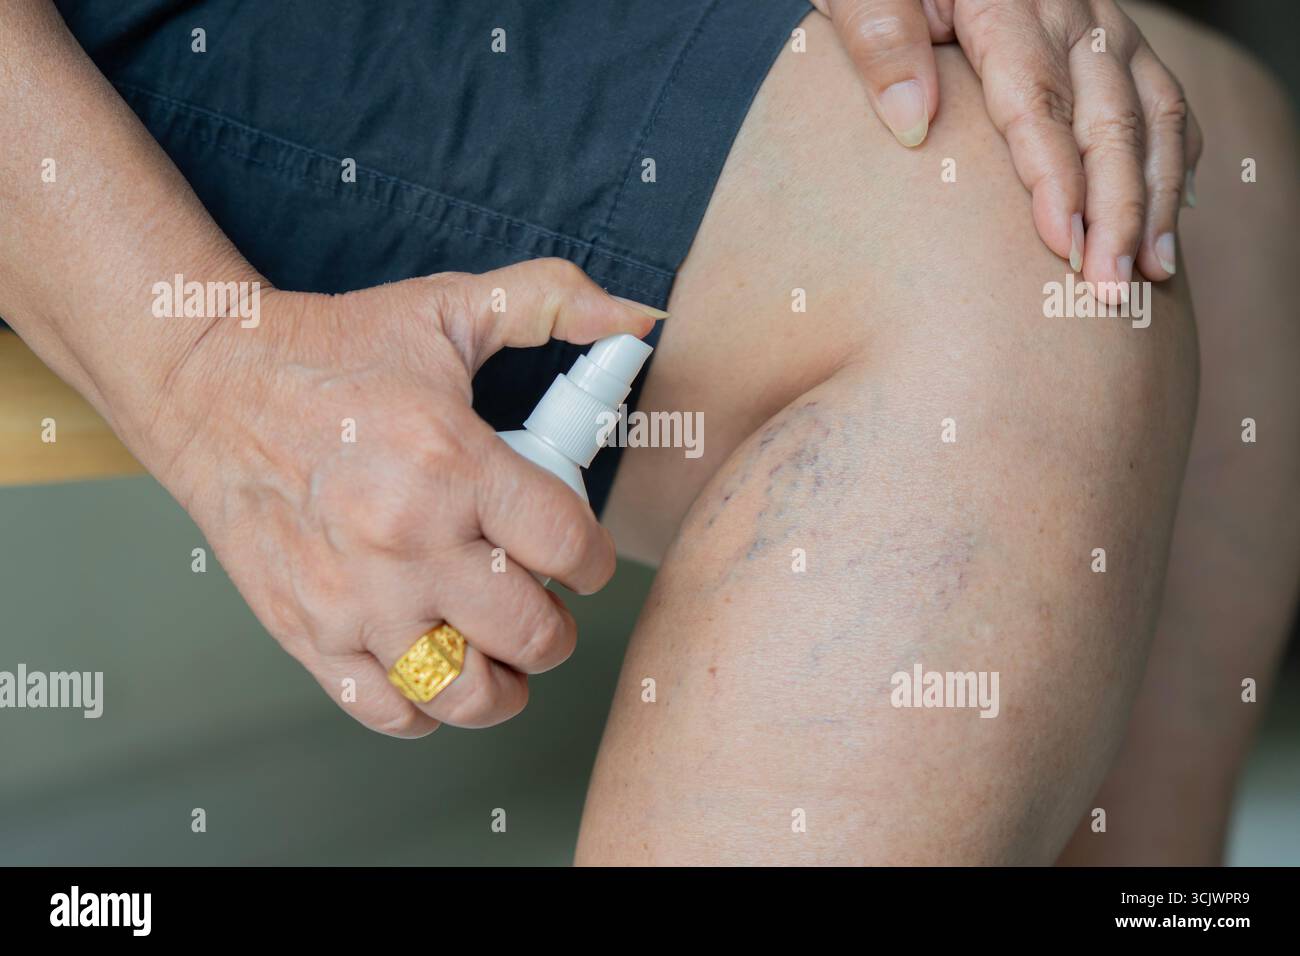

Close-up senior woman spraying medicine on thrombosis on legs Vascular disease, varicose vein problem. Treatment with medicine and cosmetology Stock Photohttps://www.alamy.com/image-license-details/?v=1https://www.alamy.com/close-up-senior-woman-spraying-medicine-on-thrombosis-on-legs-vascular-disease-varicose-vein-problem-treatment-with-medicine-and-cosmetology-image700045229.html

Close-up senior woman spraying medicine on thrombosis on legs Vascular disease, varicose vein problem. Treatment with medicine and cosmetology Stock Photohttps://www.alamy.com/image-license-details/?v=1https://www.alamy.com/close-up-senior-woman-spraying-medicine-on-thrombosis-on-legs-vascular-disease-varicose-vein-problem-treatment-with-medicine-and-cosmetology-image700045229.htmlRF3CJWPR9–Close-up senior woman spraying medicine on thrombosis on legs Vascular disease, varicose vein problem. Treatment with medicine and cosmetology